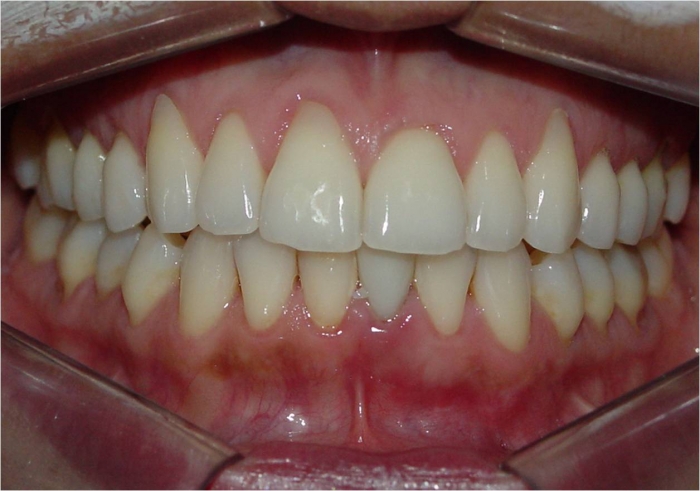

Imagem inicial

Imagem inicial do incisivo central inferior esquerdo fraturado